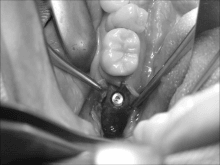

奥歯のインプラントオペ

こんにちは。 南館歯科クリニックの木村です。 右下のインプラント治療の症例をご紹介します。 部位は第2大臼歯といわれる 一番奥の歯になりますが さらに奥にオヤシラズがあり そのままではスペース的に イ…